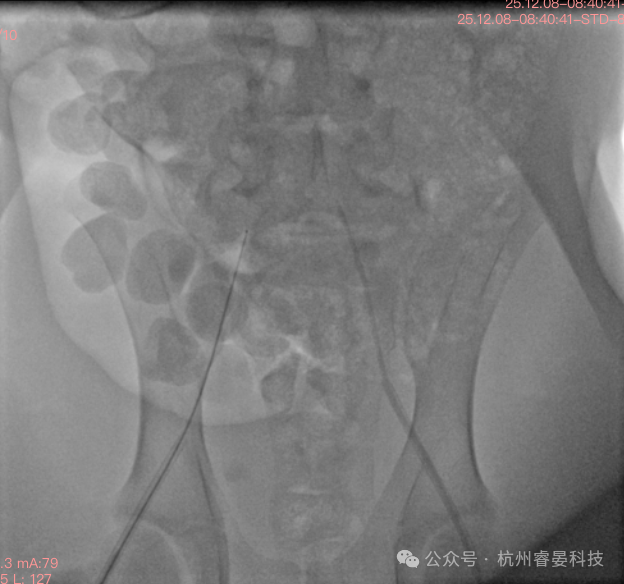

▲ 置鞘影像

导管植入:穿刺动脉壁,将预充满肝素生理盐水的压力测定导管向心方向插入。根据测量长度,将导管前端送入髂总动脉位置。

实时监测:导管尾端连接压力传感器与血流动力学记录仪, 实时记录各项动脉压力。